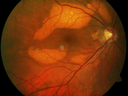

Multifocal Vitelliform Macular Dystrophy547 views58 year old female with mild vision loss - 20/20 OU - extensive testing has shown no cancer. Case of Karina Findlay, MD